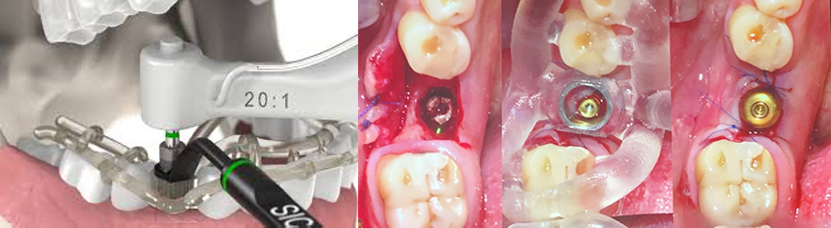

Ψηφιακή Ροή-Fully Guided Implant Surgery

Στη συνέχεια, με τη βοήθεια κατάλληλου λογισμικού, επιλέγεται το είδος του εμφυτεύματος και οι διαστάσεις του και τοποθετείται αυτό στην ακριβή του θέση στη γνάθο μέσα στο πρόγραμμα.

Στη συνέχεια κατασκευάζεται κατάλληλος χειρουργικός νάρθηκας, και εκτυπώνεται με τρισδιάστατο εκτυπωτή -3D printer- που θα καθοδηγήσει τον επεμβαίνοντα ώστε να τοποθετήσει τα εμφυτεύματα στην ακριβή θέση που έχει προεπιλεγεί μέσα από τον υπολογιστή έχοντας υπόψιν τη θέση των ανατομικών μορίων που θέλουμε να αποφύγουμε και την ποσότητα και ποιότητα του οστού.

Η ακρίβεια και η ασφάλεια του συστήματος είναι τόσο μεγάλη που δεν είναι καν απαραίτητο να ανοιχτεί κρημνός –flapless-, γεγονός που σημαίνει ότι ο ασθενής δεν έχει τομές και δε χρειάζεται καν ράμματα! Η τοποθέτηση των εμφυτευμάτων είναι όσο το δυνατόν ατραυματική και σύντομη και οι πιθανότητες επιπλοκής όπως πχ οίδημα (πρήξιμο) κλπ.